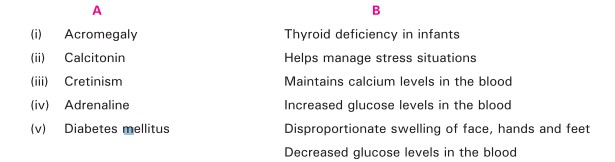

Q-7 Match the column: